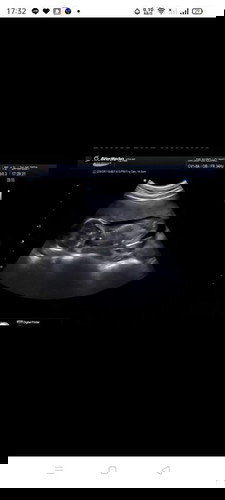

ตั้งครรภ์ได้ 16 สัปดาห์ อัลตราซาวด์แล้วน้องนอนคว่ำแบบนี้ เป็นอะไรมั้ยค่ะ